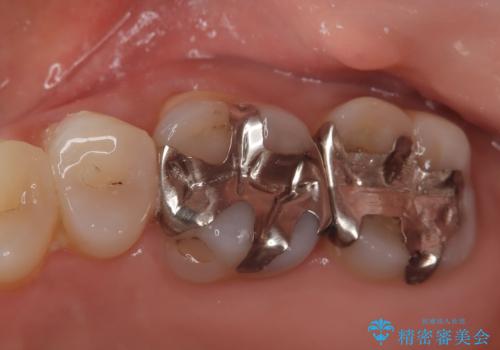

【メタルフリー】セラミックインレーの修復

- メタルフリーを希望された患者さんです。

金属を除去し虫歯の処置をしたあとセラミックインレーにて修復しました。